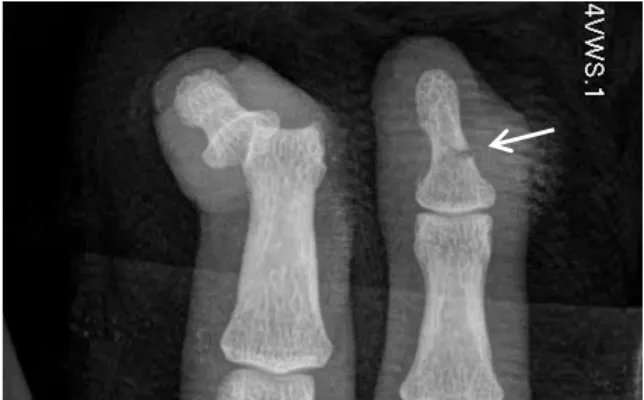

Fractura vertebral en la unión toracolumbar (D12–L1)

Fractura vertebral en la unión toracolumbar (D12–L1) Presentación Edad: N/A Género: Femenino Radiografías AP y…